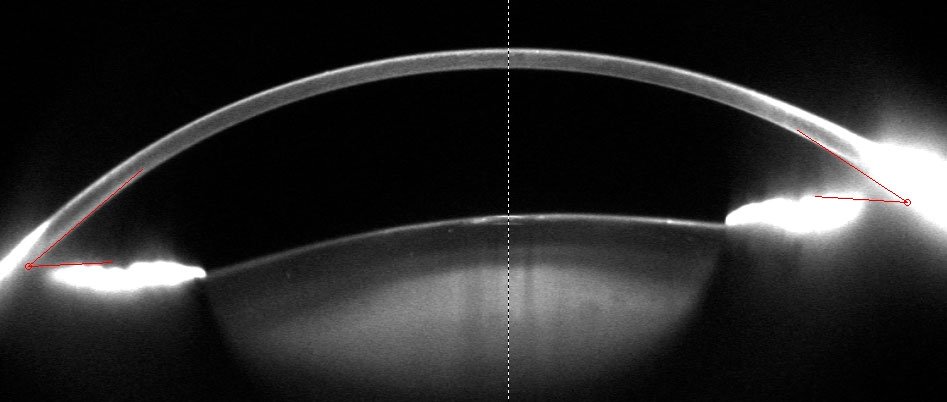

Catratas pentacam